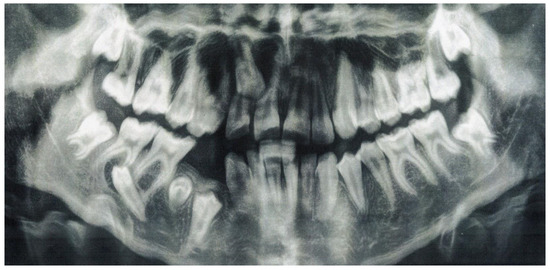

Tooth Migration in a Female Patient with Hyperdontia: 11-Year Follow-Up Case Report

2. Case Report